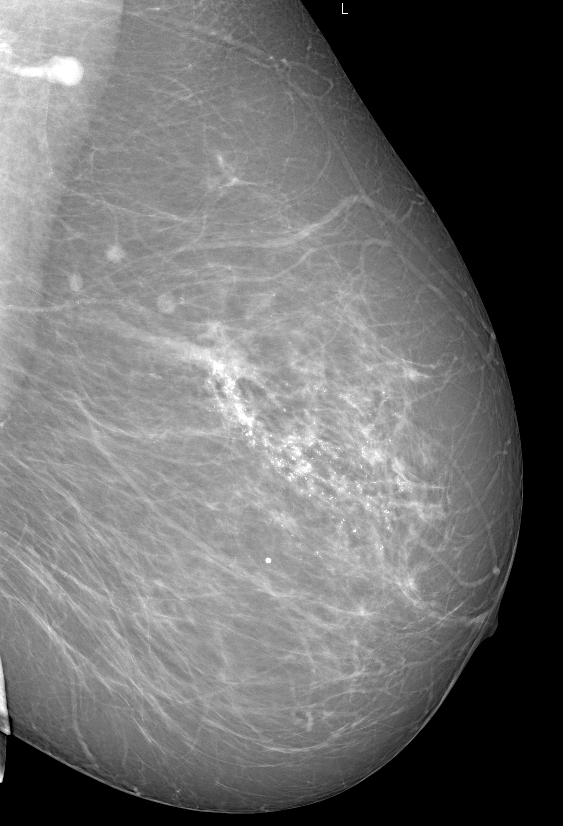

Что такое маммография: важность, процесс и результаты

Раздел: Необычные решения